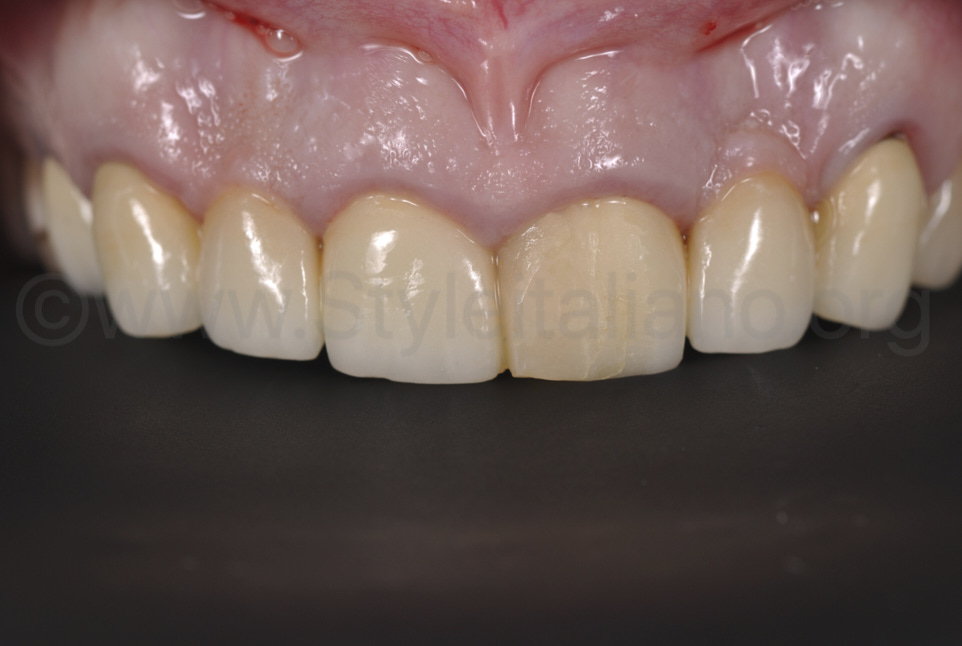

Фото 13.

Одразу після завершення операції можна було помітити ефект збільшення об’єму ясен внаслідок введення сполучнотканинного трансплантата, що значною мірою покращило зовнішній вигляд. Отже, можна відразу створювати ідеальну бажану форму зубів, заплановану на wax-up, а потім клінічну ситуацію адаптувати до неї. Повторимо, загоєння ясен залежатиме від форми зубів. Тому ми вважаємо, що проведення пластичної операції одночасно зі встановленням кінцевої реставрації позитивно впливає на кінцевий результат лікування.